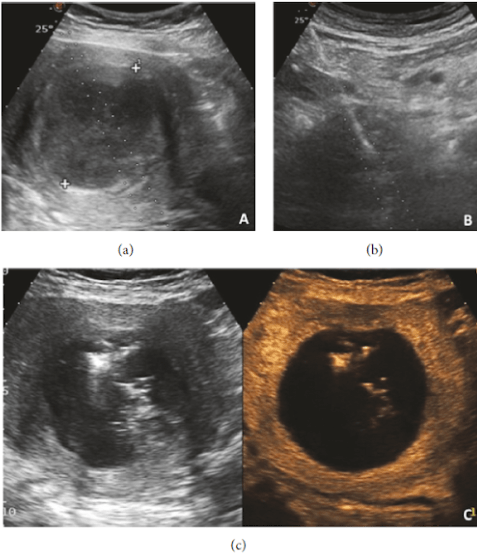

Todo o procedimento é guiado por ultrassonografia pélvica, para o adequado posicionamento da antena no interior do mioma, diferentemente da radiofrequência, em que a agulha é inserida no mioma pela via transvaginal.

Existem diversos trabalhos científicos (ensaios clínicos) publicados com a ablação dos miomas com micro-ondas, com resultados muito favoráveis ao método e baixo risco de complicações.

Foram incluídas 671 mulheres com miomas uterinos sintomáticos.

A redução média no volume do mioma uterino de 85%.

Redução significativa dos sintomas relacionados com os miomas uterinos e melhora na qualidade de vida.

Nenhum evento adverso importante, como lesão iatrogênica da bexiga, ureter ou intestino foi relatado nos 10 ensaios clínicos que fizeram parte do estudo.